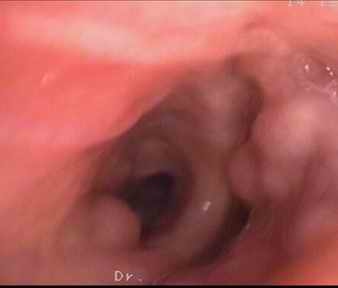

图片2 支气管镜可见管腔内结节样突起

鄞州人民医院呼吸科副主任医师徐涛说:“近9年来,老华经常会莫名咯血,象《红楼梦》中的林妹妹那样,经常会捂着手绢咳嗽,手绢上留下点点血丝。10月下旬,因为有个亲戚在宁波打工,老华从金华来到宁波,顺便请宁波医生检查 下是什么原因引起咯血。10月26日,鄞州人民医院为老华检查后发现,老华左肺部有大面积的炎症。为了确定是什么原因导致的,决定10月31日给他作气管镜检查,以确诊出血原因。检查时,结果发现他气管里有好几个突起的球形状。按照常规,气管镜检查后要对可疑处采样活检。意想不到是,经对老华气管突起的球形状部位采样后,老华突然出血,大口大口从口腔和鼻腔喷出鲜血,近2000ml,引起失血性休克。为防止患者因气道堵塞危及生命,闻讯赶来的呼吸科博士、副院长俞万钧立即组织现场抢救。医生对患者实施现场急救,并紧急请求麻醉科、ICU、介入科等专家前来抢救。近2个小时中,患者经麻醉科专家实施双腔气管插管并进行支气管镜镜下治疗、介入科专家在DSA下对其气管内破损的血管实施介入止血手术以及输入鲜血1600毫升、血浆1200毫升及大量液体后,终于把老华拖离了鬼门关。